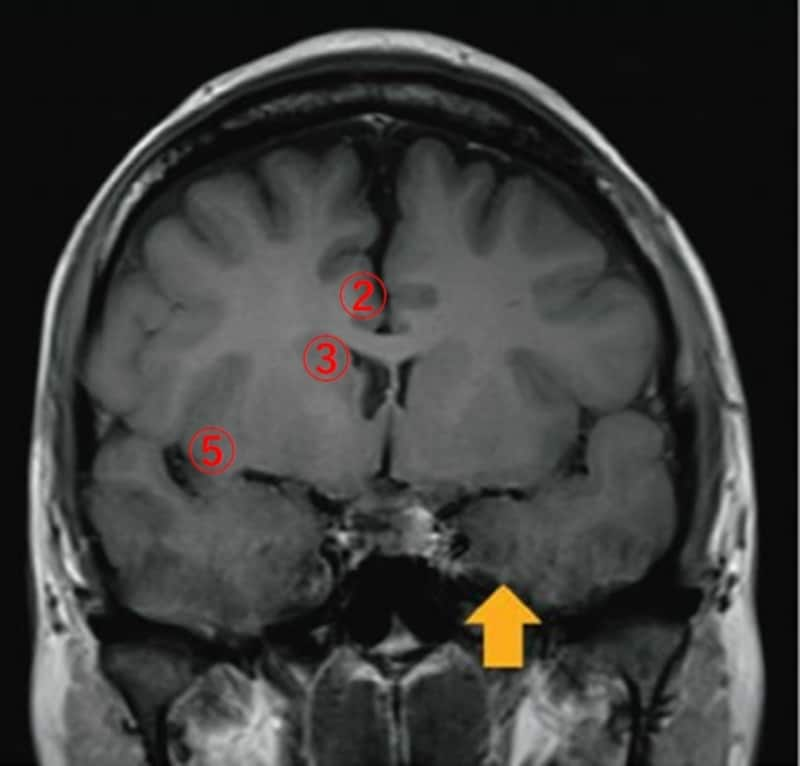

過去問題 第52回(2017年)頭部MRIのT1強調冠状断像を図に示す。矢印の部位はどれか。

- 前頭弁蓋

- 帯状回

- 尾状核

- 海馬

- 島

この答えは【4】の海馬になります。MRI画像はここ10年の国家試験において、共通問題、専門問題問わず必須となっていますので、参考文献などを通じ、しっかり学習することをおすすめします。なお、問いの解答ですが、1の前頭弁蓋に関しては、中心前溝下部と 外側溝上行枝の領域であり、島皮質を覆うようにして存在します。他の領域については画像にて下記画像を確認してください。